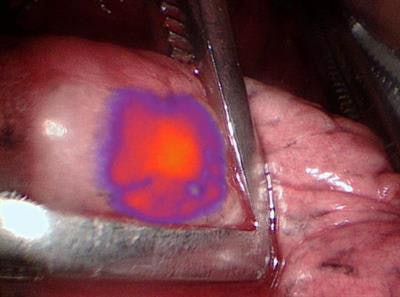

Preliminary results from a pilot trial, published online July 25 in the Annals of Surgery, show how the infrared agent, OTL38, makes tumor cells glow, allowing clinicians to detect malignant lung nodules as small as 0.5 mm. When used with intraoperative molecular imaging, OTL38 guidance was also credited with finding more lesions that went unseen in preoperative PET/CT scans.

Participants also intravenously received 0.025 mg/kg of OTL38 three to six hours before resection. When it came time for the resection, clinicians used the fluorescence of the nodules as part of the intraoperative molecular imaging and surgical procedure. Real-time fluorescent imaging was done with a high-definition camera that could emit and detect light in the near-infrared spectrum, thus detecting OTL38.

During the operation, the intraoperative molecular imaging technique with OTL38 identified 60 (91%) of the 66 pulmonary nodules detected with preoperative imaging. IMI with OTL38 also detected nine additional malignant lesions that were not seen on preoperative scans. The findings prompted clinically upstaging for six (12%) of the 50 patients and altered the care management for 15 (30%) subjects.

IMI with OTL38 also was able to identify nodules as small as 0.5 cm, compared with preoperatively detected nodules of 2.4 cm by PET/CT (p < 0.01), even though fluorescence was similar in both situation (tumor-to-background ratio 3.3 and 3.1, respectively; p = 0.50).

"OTL38 seems to do an excellent job of not only characterizing those nodules that were identified preoperatively, but also helping to characterize and identify nodules that are below the threshold of PET detection," Predina said. "So we are able to find a number of nodules even down to the 1-mm range."